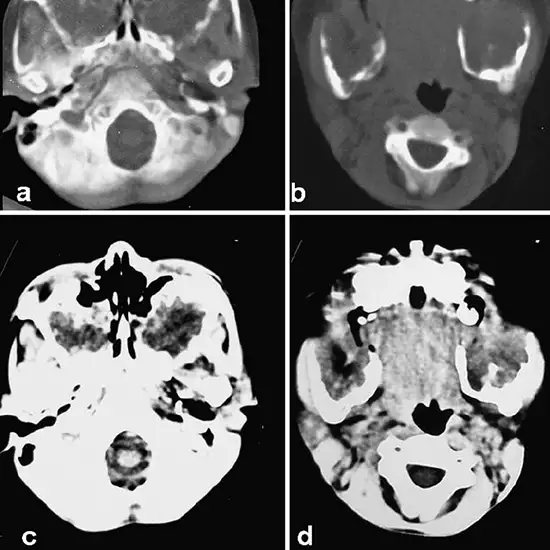

Your physician has ordered a computed tomography (CT) scan of your mandible and/or maxilla. The lower jaw is referred to as the mandible. The upper jaw is referred to as the maxilla. CT scans create detailed images of the body using X-ray technology and advanced computer analysis. A CT scan of the mandible/maxilla can assist your doctor in determining any injury, infection, or other abnormalities.

Injuries, infections, tumours, and other anomalies